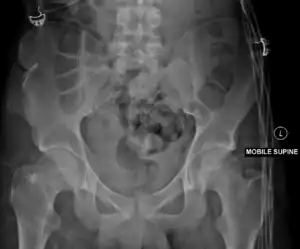

Duverney fractures are isolated pelvic fractures involving only the iliac wing. They are caused by direct trauma to the iliac wing, and are generally stable fractures as they do not disrupt the weight bearing pelvic ring.[1]

Duverney fractures can usually be seen on pelvic X-rays, but CT scans are required to fully delineate the fracture and to look for associated fractures involving the pelvic ring.[3]